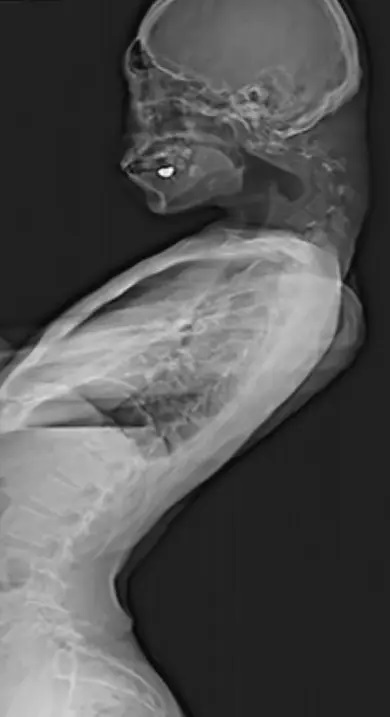

وتظهر الصور المروعة انتفاخا بارزا من رقبته، والذي عزاه المسعفون إلى "تمدد فقراته بشكل كبير" عن الوضع غير الطبيعي، بحسب ما نقلت "ديلي ميل".

وكشفت صور الأشعة التي أجراها أطباؤه أن فقرات رقبته قد تشوهت وانخلعت، مما أدى إلى نمو أنسجة تشبه الندبات في العمود الفقري بمرور الوقت.

واختار الأطباء بدلا من ذلك سلسلة من العمليات الجراحية، وقاموا أولا بإزالة أجزاء صغيرة من فقراته وبعض الأنسجة الشبيهة بالندبات التي تكونت في رقبته. ثم أدخل الأطباء سلسلة من البراغي والقضبان المعدنية في عظام رقبته لتصحيح وضعيته، وبعد ستة أشهر من الجراحة وجد الأطباء تحسنا ملحوظا على المريض وتحسنت قدرته على رفع رأسه والنظر أفقيا.